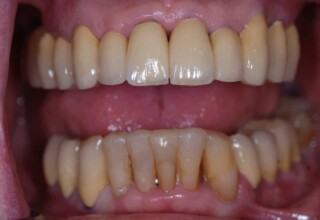

Ολική Στοματική Αποκατάσταση σε Εμφυτεύματα με διαφορετική προσέγγιση στην Άνω και Κάτω Γνάθο

Κάτω γνάθος: εξαγωγές, άμεση τοποθέτηση εμφυτευμάτων και άμεση φόρτιση(την ίδια ημέρα) με προσωρινή γέφυρα

Άνω γνάθος: σταδιακές εξαγωγές, σταδιακή τοποθέτηση εμφυτευμάτων και σταδιακή ενσωμάτωση τους στην προσωρινή γέφυρα ώστε η ασθενής να μην μείνει ούτε μια ημέρα χωρίς αποκατάσταση. Στόχος η συνεχής λειτουργική και αισθητική αποκατάσταση της ασθενούς χωρίς άμεση φόρτιση των εμφυτευμάτων λόγω ανατομικών ιδιαιτεροτήτων.

Χρησιμοποιήθηκαν παλαιές χαμογελαστές φωτογραφίες της ασθενούς γιατί είχε χαθεί τελείως το φυσικό σχήμα των δοντιών εξαιτίας των πολλαπλών προσθετικών προσπαθειών που είχαν γίνει στο παρελθόν. Μεταφέρθηκε στην προσωρινή γέφυρα η σχέση των φυσικών δοντιών μεταξύ τους άλλα και με τα χείλη. Δοκιμάστηκε η φώνηση και η μάσηση με δυο διαφορετικές προσωρινές άνω γέφυρες και εκτιμήθηκε η αισθητική απόδοση τους. Αφού επιτεύχθηκαν σε βαθμό ικανοποιητικό η φώνηση και η αισθητική εμφάνιση της οδοντοφυΐας, η προσωρινή αποκατάσταση χρησιμοποιήθηκε ως οδηγός για την τελική.

Τελικό